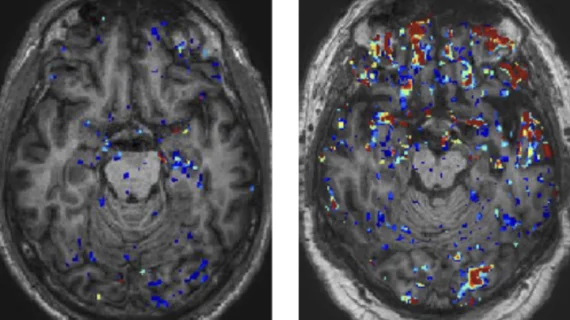

Up to 25% of physically unresponsive patients are still conscious, imaging shows

The phenomenon, known as cognitive motor dissociation, might occur more often than previously believed.

Study calls for MRI follow-up in concussion patients

Follow-up MRI in patients with mild traumatic brain injuries could help predict if they will experience lingering symptoms months later, even if their initial imaging was normal.